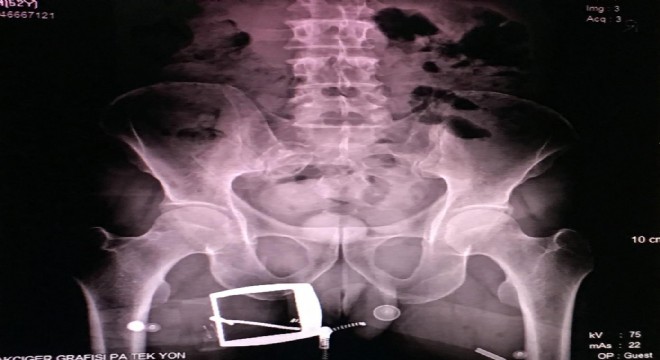

Erzurum'da, makatında gizlediği uyuşturucuyu İstanbul’a götürmek isteyen İran uyruklu kadın narkotik polisine yakalandı. Kadının taşıdığı uyuşturucular röntgen çekilerek bulundu.

Erzurum Emniyet Müdürlüğü Kaçakçılık ve Organize Suçlarla Mücadele (KOM) Şubesi ekipleri, uygulama sırasında durdurdukları bir yolcu otobüsünde arama yaptı. İranlı B.H.’ye ait olduğu anlaşılan valizde, 21 parçadan oluşan ve ‘met’ olarak bilinen 607 gram ‘metamfetamin’ maddesi ele geçirildi. Gözaltına alınan B.H.’nin hareketlerinden şüphelenen narkotik polisi, kendisini sağlık kontrolü için hastaneye götürdüğünde röntgen çekilmesini de istedi. Röntgen filmi sonuçlarında İranlı kadının uyuşturucuyu kapsüller halinde makatına soktuğu anlaşıldı.

Tıbbi müdahaleyle 4 kapsül halinde 96 gram ‘met’ ve bir kapsülde 28 gram reçine esrar çıkarılırken, uyuşturucunun piyasa değerinin 50 bin lira olduğu belirtildi. İranlı B.H. tutuklanarak cezaevine konuldu.